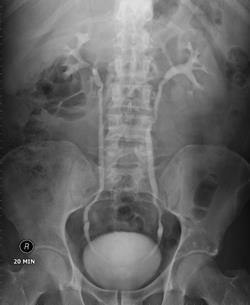

Рентгенологічне дослідження шлунку (мал. 2 В), кишківника (іригоскопія), нирок (екскреторна урографія мал. 2 Г), жовчного міхура (холецистографія мал. 2 Д).

мал. 9 нирки

Мал. 2 Г. Екскреторна урографія

6.3. Підготовка пацієнта до рентгенологічного дослідження нирок і сечовивідних шляхів (екскреторної урографії)

Попередня підготовка

Основні етапи виконання:

1. За відсутності ознак йодизму безпосередньо перед обстеженням ввести пацієнту внутрішньовенно 20–60 мл контрастної речовини. Введення має бути дуже повільним. Під час введення медична сестра постійно спостерігає за станом пацієнта.

2. Після цього лікар проводить рентгенологічне дослідження нирок та сечовивідних шляхів.

Заключний етап: медична сестра проводить дезінфекцію використаного обладнання згідно з інструкцією. Знімає рукавички, миє руки, осушує їх одноразовим рушником, обробляє антисептиком. Робить запис у відповідній медичній документації.